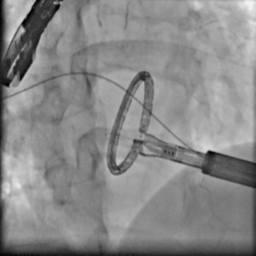

手术过程造影

手术在厦心杂交手术室进行,患者处于全麻状态,在实时三维食道超声的指引下,心外科在患者左胸前切开4-5cm的切口,经心尖预缝荷包区域导入AMEND成形环植入系统,顺利通过二尖瓣结构中央区域进入左心房后,在体外操作AMEND系统将“D”型成型环在主动脉瓣与二尖瓣间极为狭小的空间内精确释放,并先后铆钉二尖瓣环的后叶及前叶,从而达到缩小二尖瓣环的目的(图2),这一步操作要求非常精准,稍有不慎便会损伤周围组织,引起并发症。术后即刻,患者二尖瓣反流明显减轻,达到轻度水平(图3),手术从麻醉到结束平均历时3个小时。